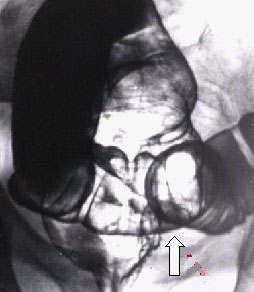

Рак толстой кишки.

Рис. 4. Полиповидный рак нижнеампулярного отдела прямой кишки в виде внутрипросветного образования с втяжением стенки кишки в основании его (стрелка).

Предоставил Дементьев Е.З.

Радиология-практика 2004 2: 48-56